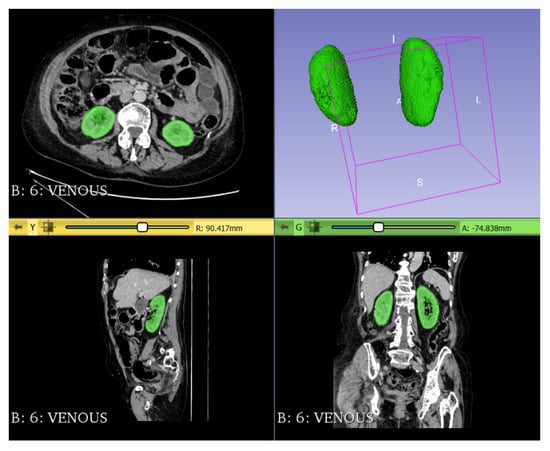

| Kidney volume/height | 0.679 | 0.585–0.773 | <0.001 |

| Mean kidney volume/height ± SD (cm3/m) | 85.7 (69.7–104.5) | 89.1 (73.6–105.7) | 66.7 (53.6–93.6) | <0.001 |

| Number of patients with kidney volume/height under cut-off point | 79 (30.27) | 49 (22.8%) | 30 (65.2%) | <0.001 |